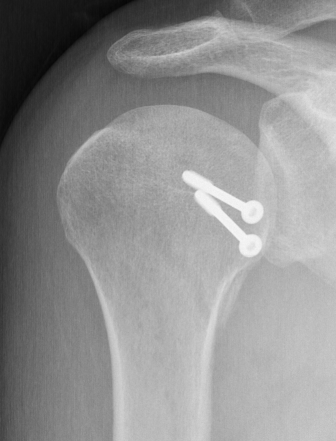

Screw fixation

LT ORIFLT ORIF

Screw + soft tissue washer

LTLTlt